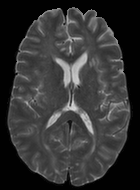

Patch size is another important parameter of the network. In computer vision applications such as object detection, usually a whole 2D image is used as a feature. However, full 3D medical images can not typically be used because of memory limitations. Fig. 4 shows examples of lesion memberships obtained with different sized 2D patches. As the patch sizes increases, the false positives that are mostly observed in the cortex tend to decrease. Fig. 5 shows a plot of Dice and LFPR with various patch sizes, ordered from left to right according to their increasing size. Note that smaller patches ( to ) produced significantly lower Dice and higher LFPR compared to other patches (), as seen from the memberships in Fig. 4. Also some of the highest Dice and lowest LFPR were observed for patches with large in-plane size, i.e., , , and . It was observed in Fig. 5 that there is no significant difference between Dice coefficients for , , or , but LFPR of both and are significantly lower than that of (). We chose as the optimal patch size. Other choices of smaller and patches (not shown) yielded worse results. Note that although training was performed with different patch sizes, the memberships were generated slice by slice, as the trained model consisted only of convolutions and did not need any information about patch sizes.